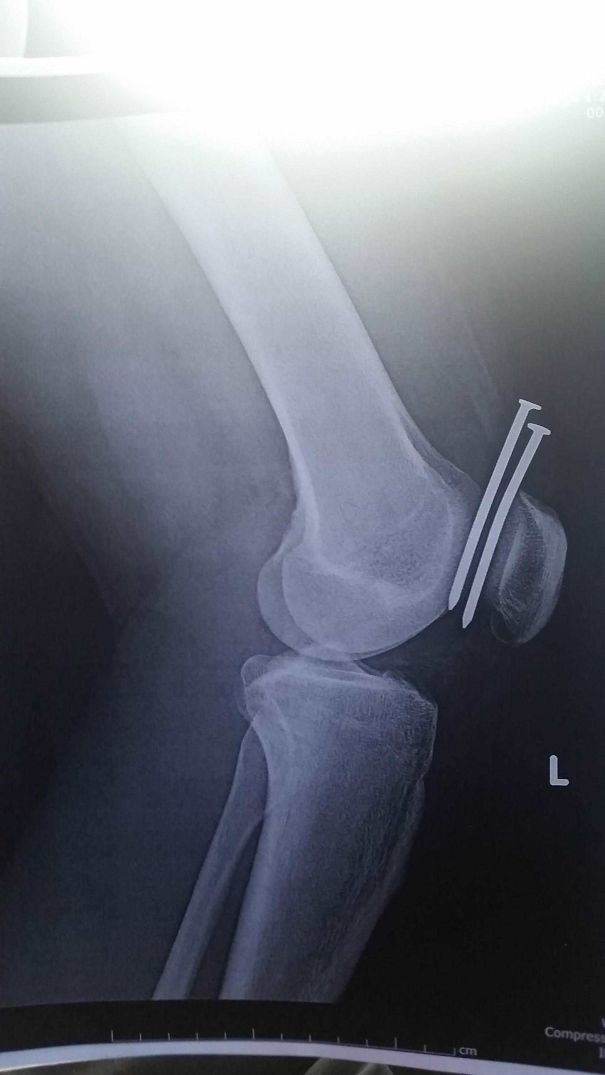

៤. បុរសម្នាក់ប្រើម៉ាស៊ីនបាញ់ដែកគោលភ្លាត់ស្នៀតបាញ់ចូលជើងទៅវិញ សំណាងល្អមិនចំឆ្អឹងជង្គង់ បែរជាចំចន្លោះវិញ